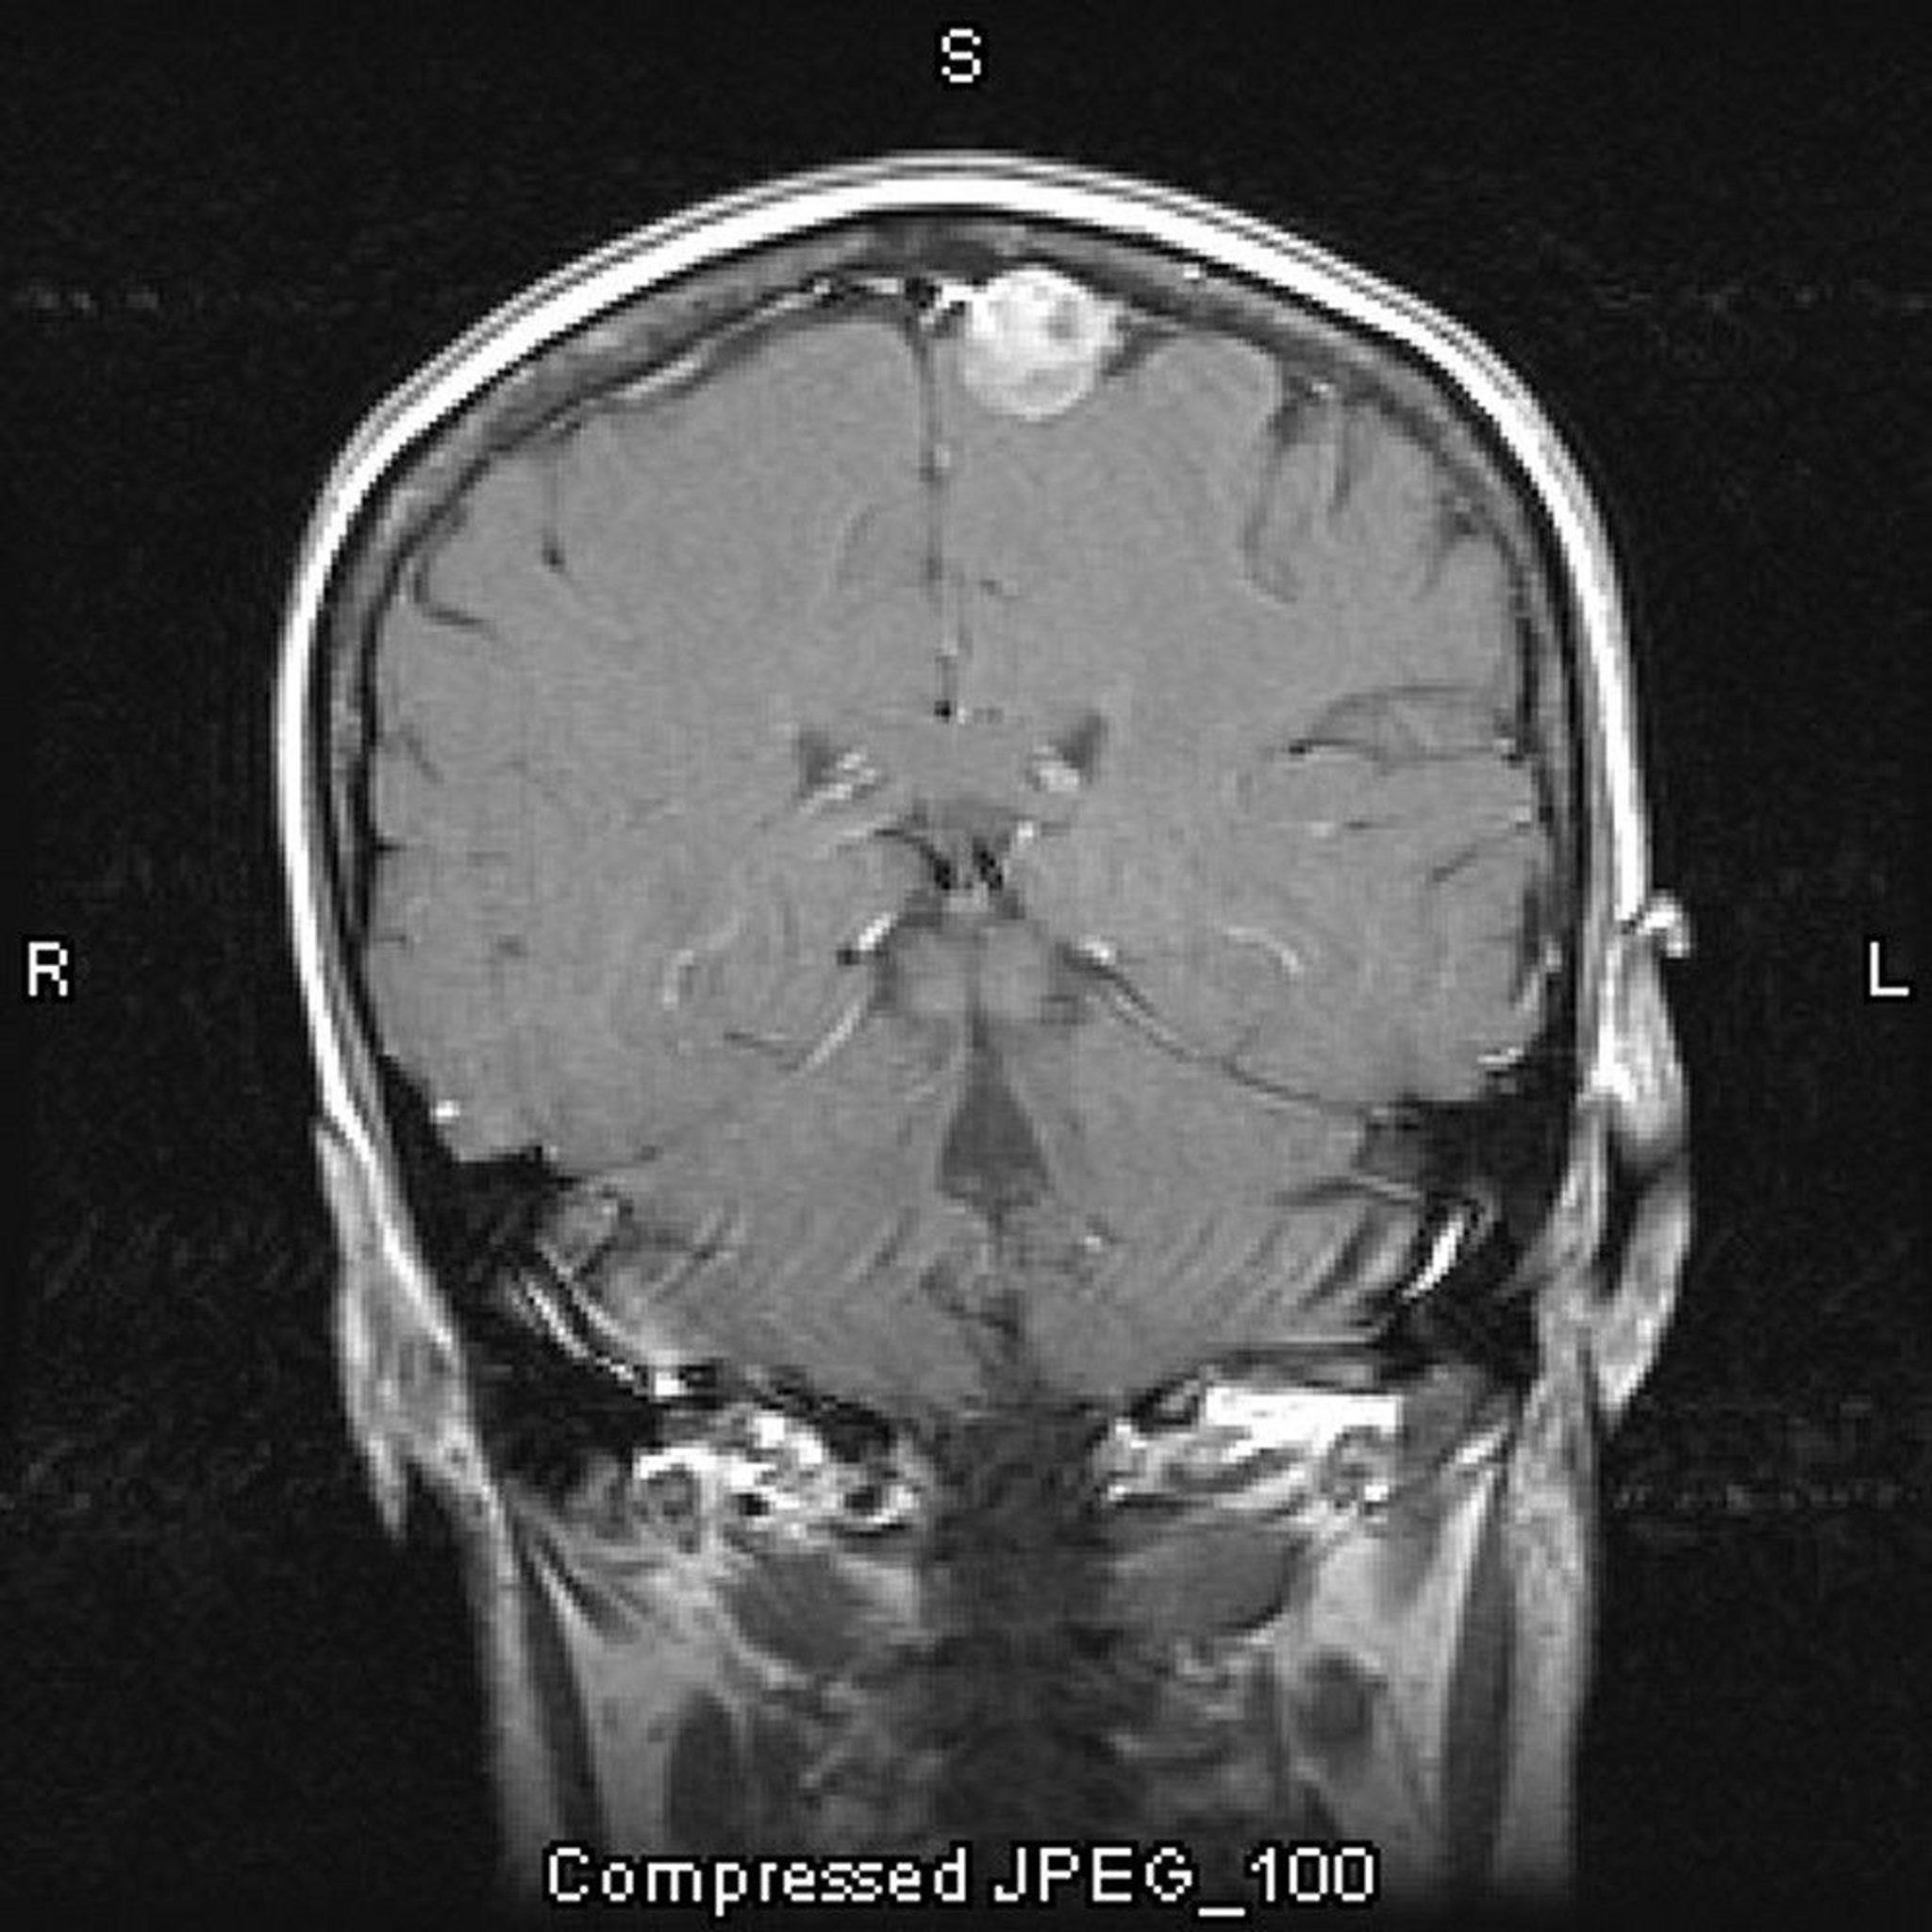

Meningioma, Parasagittal

This contrast-enhanced MRI scan shows a meningioma. The parasagittal location is a typical one for meningiomas.

Image courtesy of William R. Shapiro, MD.